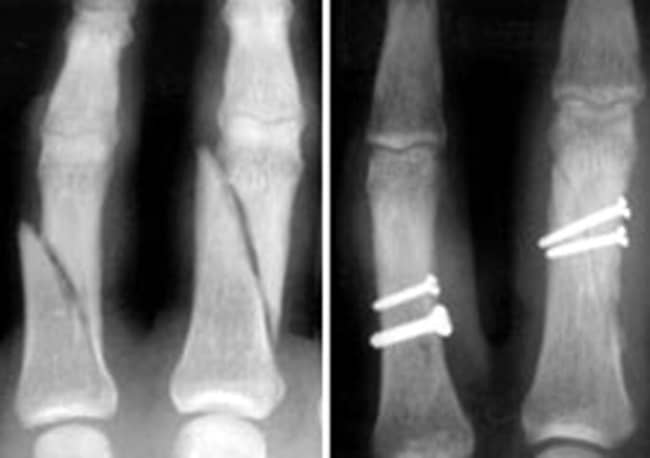

Depending on the type and severity of the fracture, you may need surgery to put the bones into alignment and keep them there while they heal.

• Small devices, such as pins, screws, plates, or wires, will be used to hold your fractured bones together. Sometimes, these devices can stay in for life, and sometimes they need to be removed after the fracture heals.

Fractured Phalanges Repaired With Screws

(Left) X-ray shows fractures in the phalanges of two fingers. (Right) In this X-ray, the fractures have been repaired with screws.

Reproduced from Kozin SH, Thoder JJ, Lieberman G: Operative Treatment of Metacarpal and Phalangeal Shaft Fractures. J Am Acad Orthop Surg 2000; 8:111-121.